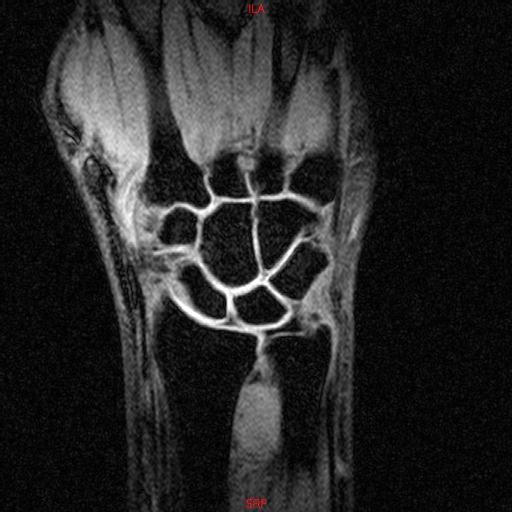

• Resonancia NORMAL MUÑECA COR T1

• Resonancia NORMAL MUÑECA COR T1 3D FATSAT